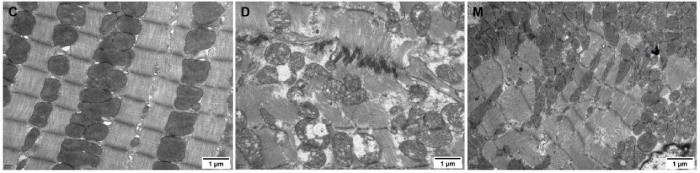

該研究利用透射電鏡測定了MOTS-c對糖尿病心肌超微結(jié)構(gòu)的影響。糖尿病引起心肌纖維排列紊亂和線粒體結(jié)構(gòu)的異常改變,包括心肌細(xì)胞排列不規(guī)則、嵴破裂、腫脹和空泡化(圖2)。MOTS-c治療糖尿病大鼠顯著降低心肌線粒體損傷,改善心肌纖維和線粒體結(jié)構(gòu)(圖2)。研究還通過測定檸檬酸合酶的活性,測定了線粒體功能。D組大鼠檸檬酸合酶的活性顯著降低,C組和M組的檸檬酸合酶的活性無統(tǒng)計(jì)學(xué)差異(圖3g)。

圖2. 各組大鼠心肌組織透射電鏡圖像